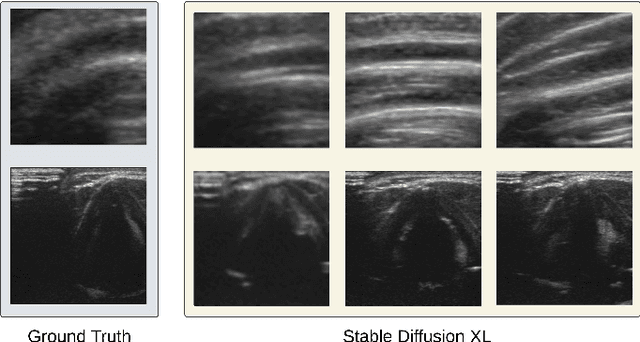

Abstract:Neck ultrasound (US) plays a vital role in airway management by providing non-invasive, real-time imaging that enables rapid and precise interventions. Deep learning-based anatomical landmark detection in neck US can further facilitate procedural efficiency. However, class imbalance within datasets, where key structures like tracheal rings and vocal folds are underrepresented, presents significant challenges for object detection models. To address this, we propose T2ID-CAS, a hybrid approach that combines a text-to-image latent diffusion model with class-aware sampling to generate high-quality synthetic samples for underrepresented classes. This approach, rarely explored in the ultrasound domain, improves the representation of minority classes. Experimental results using YOLOv9 for anatomical landmark detection in neck US demonstrated that T2ID-CAS achieved a mean Average Precision of 88.2, significantly surpassing the baseline of 66. This highlights its potential as a computationally efficient and scalable solution for mitigating class imbalance in AI-assisted ultrasound-guided interventions.